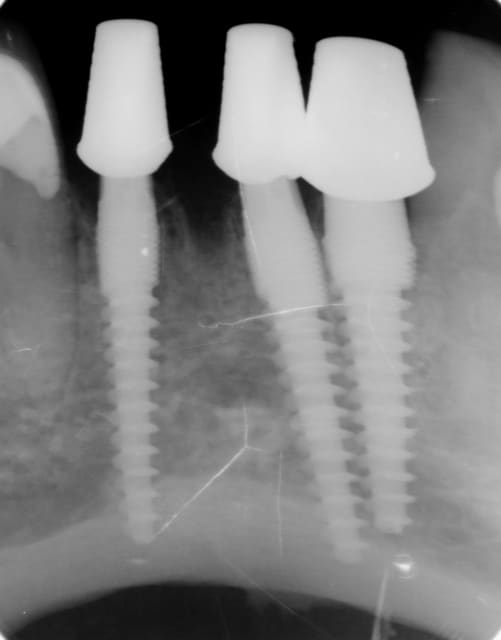

Oui tu as bien raison :-) Ci joint quelques photos en rapport avec ta question ....

Les nombreux cas déjà postés montrent que cela fonctionne et au long terme (radios après 10 ans), et que l implantologie peut être "démystifier" ( si le mot existe...) :-)